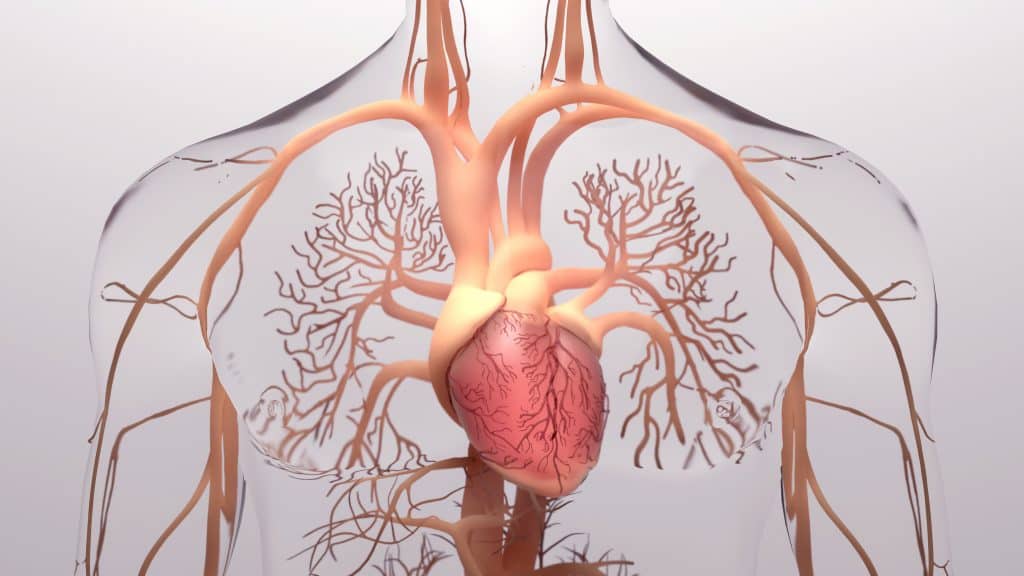

Prema studiji EHUH (Epidemiologija hipertenzije u Hrvatskoj) prevalencija arterijske hipertenzije u Hrvatskoj je 37,5% i u skladu je s rezultatima u drugim europskim državama. Učestalost znatno raste s godinama. Prije pedesete godine starosti većina ljudi ima dijastoličku hipertenziju, povišen dijastolički tlak, viši od 90 mmHg. Nakon pedesete godine života sistolički tlak neprekidno raste, a dijastolički ima tendenciju pada. U starijoj životnoj dobi sistolička arterijska hipertenzija postaje dominantna. Treba znati da je za razvoj srčanožilne i bubrežne bolesti povišen sistolički tlak važniji od povišenoga dijastoličkog tlaka.

Izolirana srčana arterijska hipertenzija povezana je sa stanjem uvećanoga udarnog volumena srca pa se može pojaviti kod sljedećih bolesti: anemije, hipertireoze, aortalne insuficijencije i arterijsko venoznih fistula.

U većini slučajeva izazvana je smanjenom elastičnošću arterija zbog starenja i aterosklerotskih nakupina kalcija, kolagena te degeneracije elastina. Tvrde provodne arterije pojačavaju reflektirani val krvi iz perifernih krvnih žila i uzrokuju porast sistoličkog tlaka. Unatoč spoznaji o povoljnom učinku smanjenja povišenoga krvnog tlaka na zdravlje ljudi, samo oko 30% liječenih hipertoničara ima poželjnu vrijednost tlaka od 140/90 mmHg ili nižu. Neodgovarajuće liječenje najčešće je uzrokovano neliječenjem izolirane arterijske hipertenzije.

Izolirana arterijska hipertenzija dovodi do ozbiljnih komplikacija kao što su: moždani udar, bolest srca, kronična bolest bubrega i demencija.